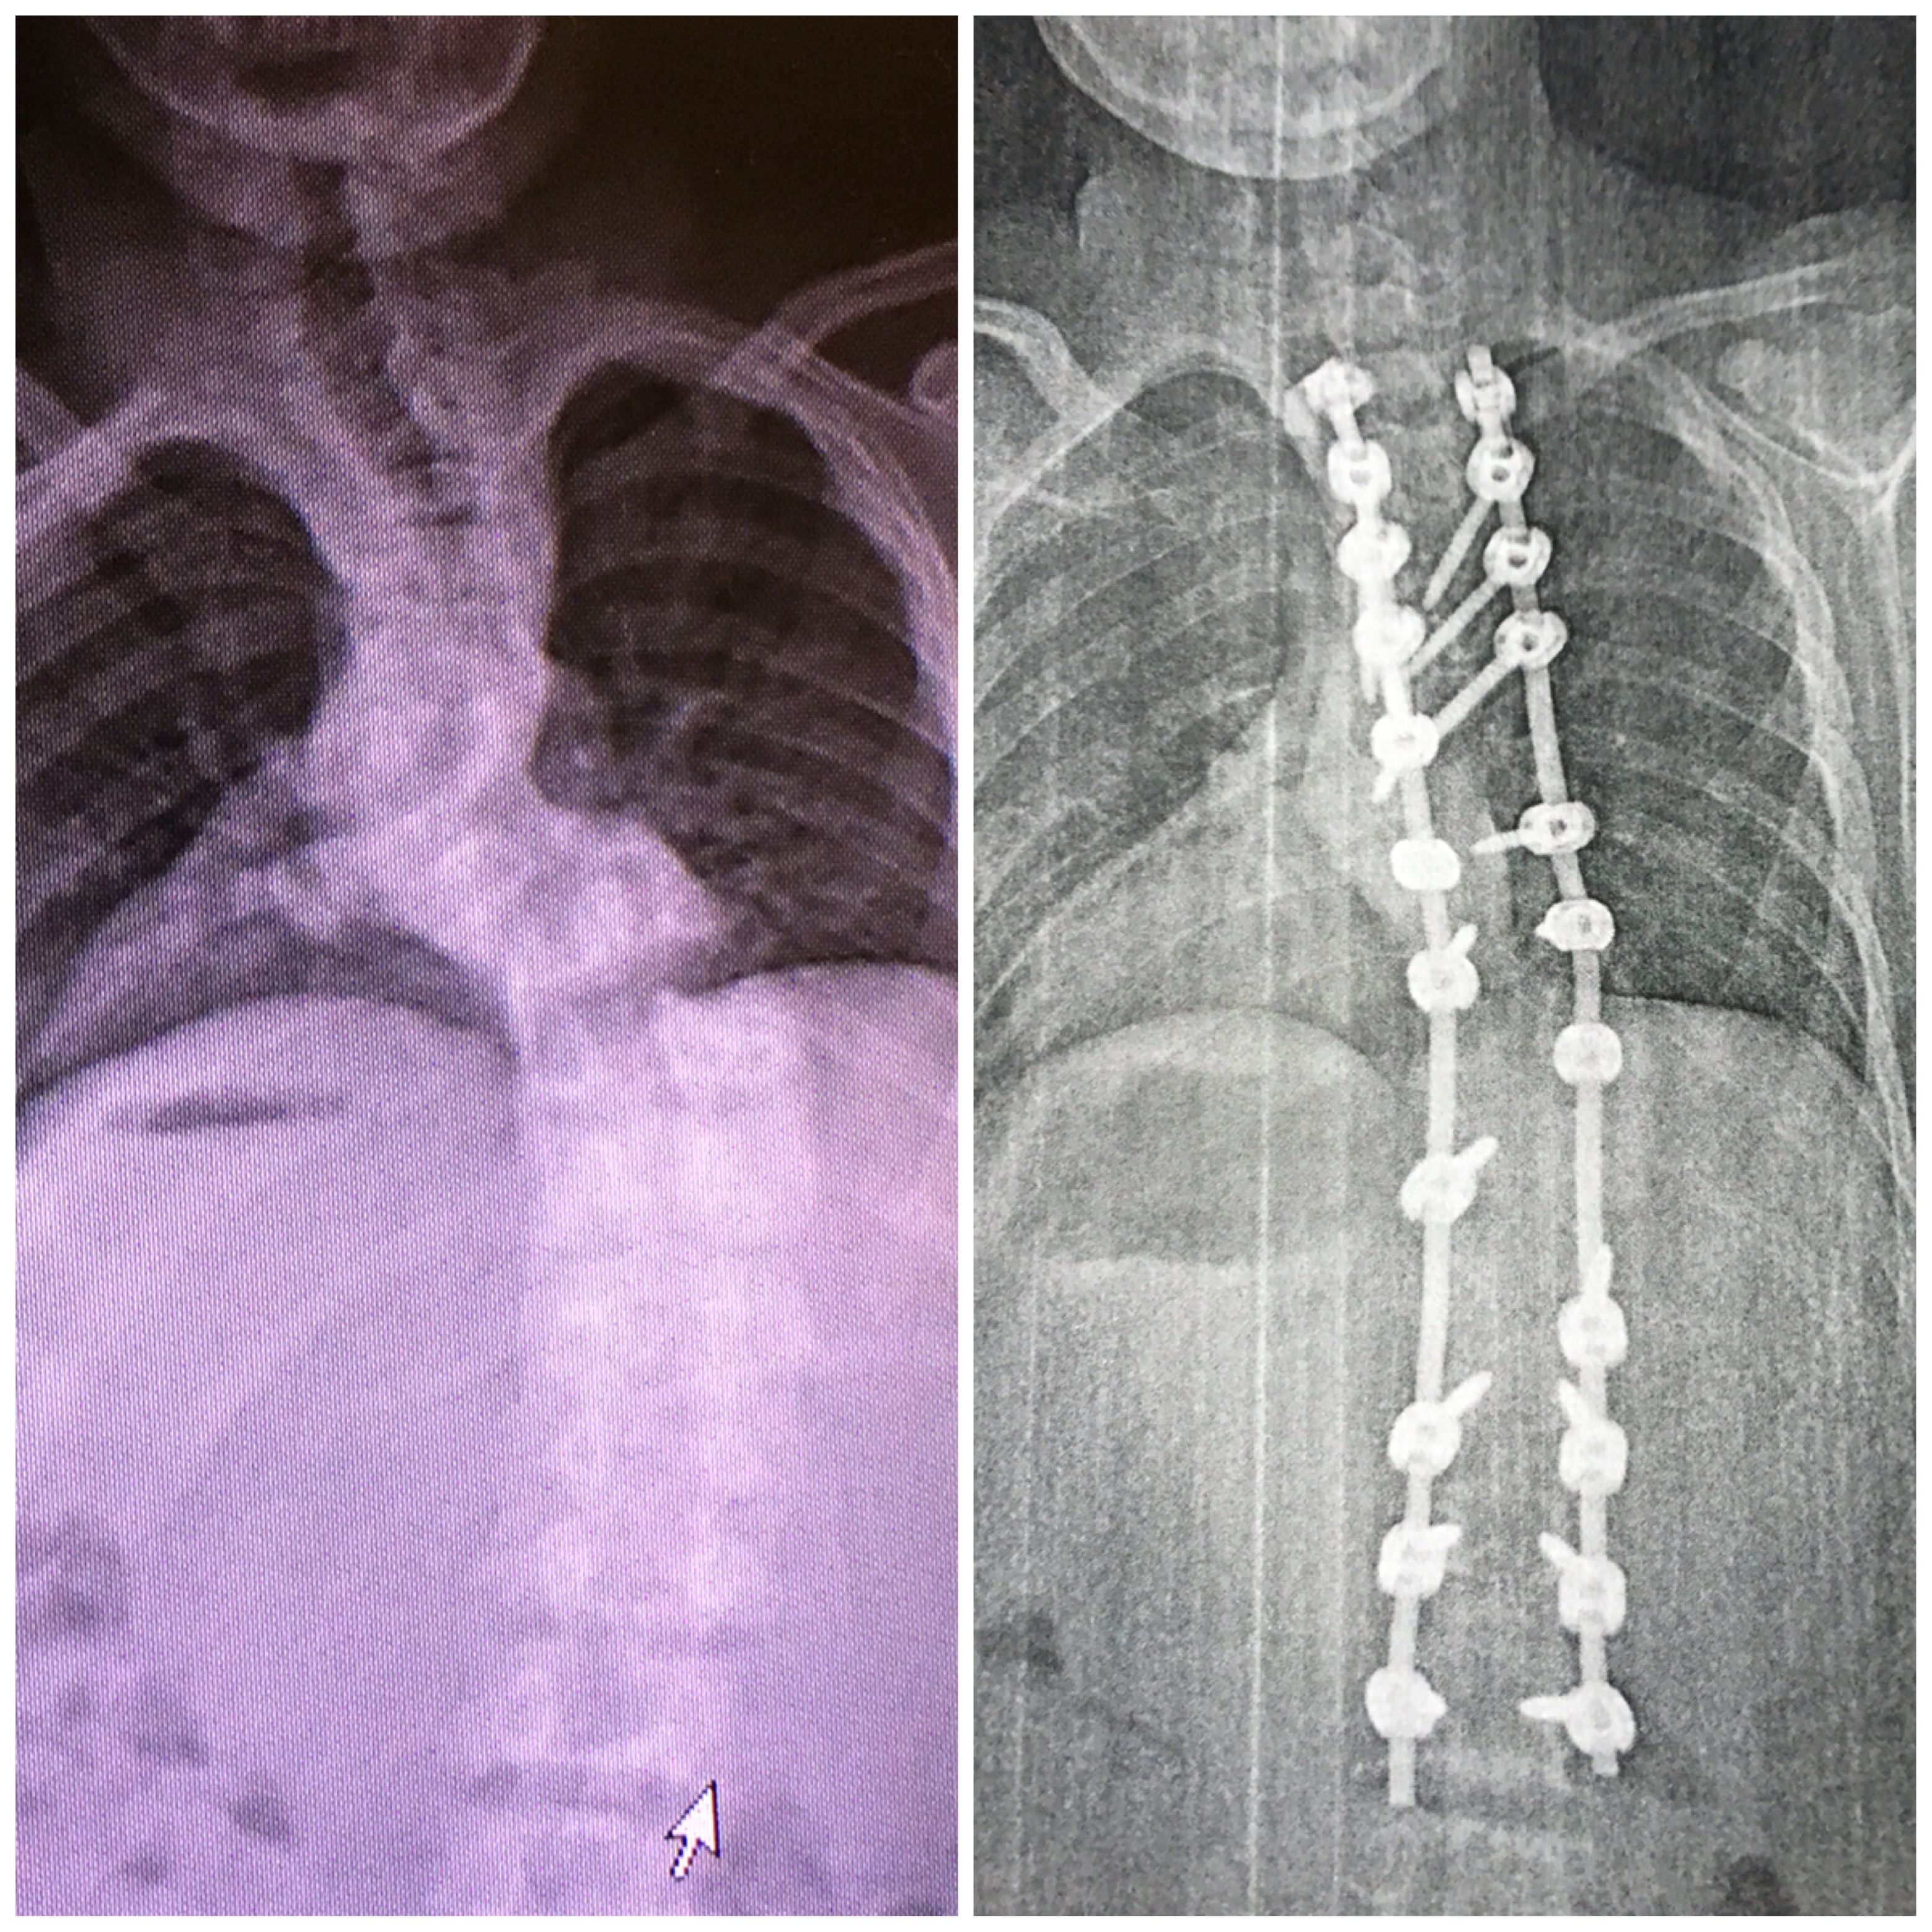

This time last year, JC was in Delaware having surgery to correct his spine. When he went for a consultation in December 2016 at Nemours, they met with Dr. McKenzie, an orthopedist. JC’s spine was at a curve of 100 degrees. Dr. McKenzie warned the family not to get their hopes up for a full recovery, but said the surgery would help JC have a more productive life.

The first surgery was May 23, 2017, where he had an anterior thoracoscopic release and a halo installation. He was in the halo for three weeks in order to get the desired spinal cord correction. The second surgery took place June 14, 2017, JC had a posterior spinal fusion from his third lumbar vertebrae to his third thoracic vertebrae.

The improvement for JC was miraculous. Today, his spine is at a curve of 45 degrees. He also gained four inches in height from the surgery. Mandy said this is a huge change for JC, not only as far as what he can do physically, but also emotionally.